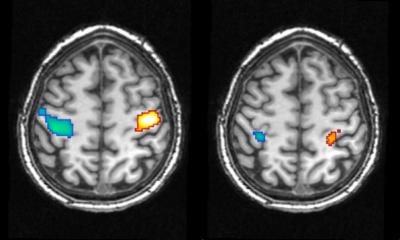

This enabled the scientists to measure the entry into REM sleep – a phase in which dreams are perceived particularly intensively – with the help of the subject's electroencephalogram (EEG) and to detect the beginning of a lucid phase. The brain activity measured from this time onwards corresponded with the arranged "dream" involving the fist clenching. A region in the sensorimotor cortex of the brain, which is responsible for the execution of movements, was actually activated during the dream. This is directly comparable with the brain activity that arises when the hand is moved while the person is awake. Even if the lucid dreamer just imagines the hand movement while awake, the sensorimotor cortex reacts in a similar way.

The coincidence of the brain activity measured during dreaming and the conscious action shows that dream content can be measured. "With this combination of sleep EEGs, imaging methods and lucid dreamers, we can measure not only simple movements during sleep but also the activity patterns in the brain during visual dream perceptions," says Martin Dresler, a researcher at the Max Planck Institute for Psychiatry.

The researchers were able to confirm the data obtained using MR imaging in another subject using a different technology. With the help of near-infrared spectroscopy, they also observed increased activity in a region of the brain that plays an important role in the planning of movements. "Our dreams are therefore not a 'sleep cinema' in which we merely observe an event passively, but involve activity in the regions of the brain that are relevant to the dream content," explains Michael Czisch, research group leader at the Max Planck Institute for Psychiatry.